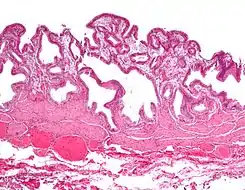

Microfotografía de colesterolosis vesicular. H&E stain.

A veces se llama vesícula biliar de fresa por el aspecto punteado de la superficie de la mucosa en un examen general, similar al que presentan las fresas. La colesterolosis está causada por una acumulación anormal de depósitos de ésteres de colesterol en macrófagos dentro de la lámina propia (células espumosas) y en el epitelio de la mucosa. La vesícula biliar puede estar afectada de forma localizada o de forma difusa. La forma difusa se presenta macroscópicamente como una mucosa roja brillante con motas amarillas (debido a los lípidos), de ahí la comparación con la fresa. No está ligada a la colelitiasis (cálculos vesiculares) ni a la colecistitis (inflamación de la vesícula biliar).[2]